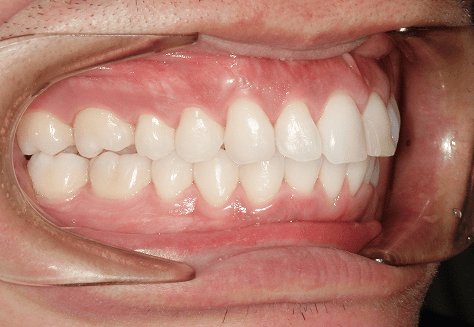

M.U

治療前

治療後

主訴

下の歯が特にガタガタなのが気になる。上の前歯が1本反対になっている。

診断

下顎前突・叢生・反対咬合

年齢/性別

20代/男性

抜歯部位

非抜歯

使用装置

上下インビザライン(PBM使用)

保定装置

ビベラリテーナー

診察料金

5,500円×16回

治療期間

1年7カ月